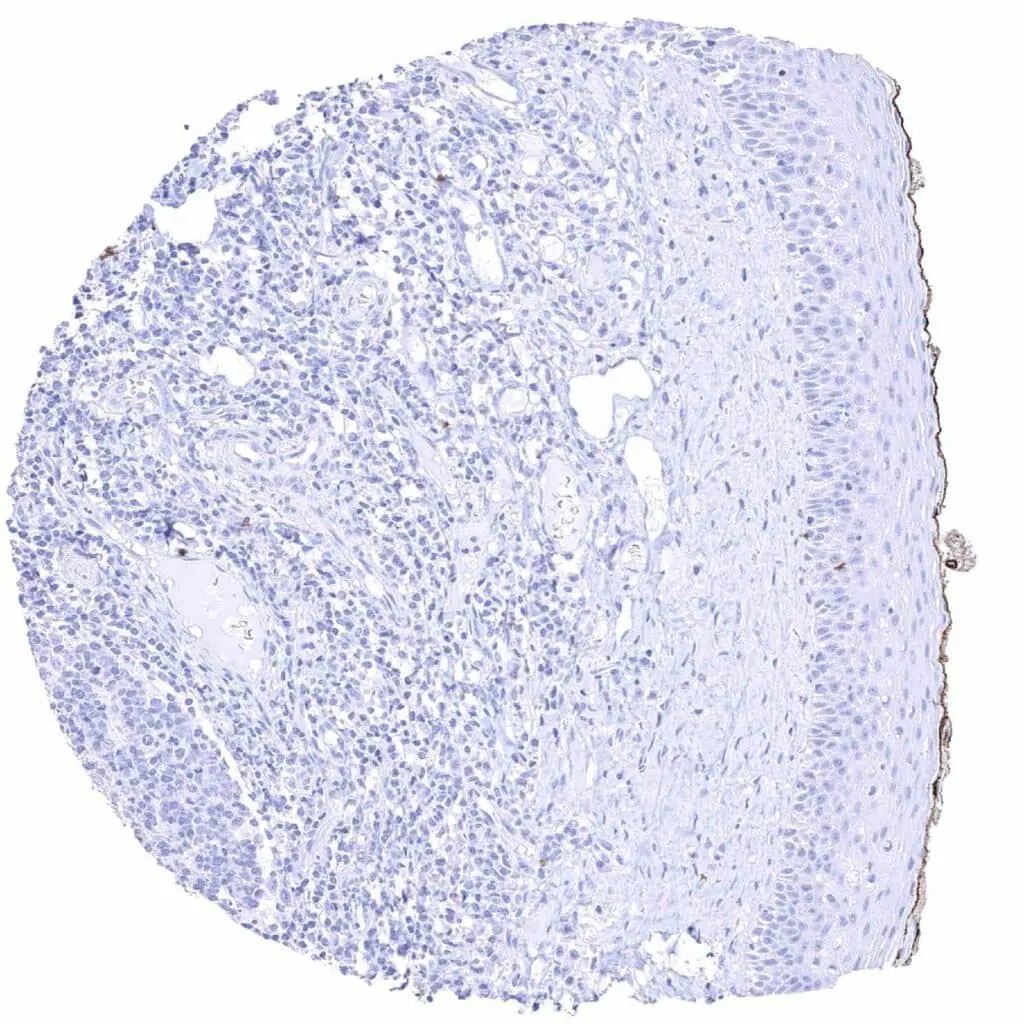

Skeletal muscle – Strong cytoplasmic MYH7 staining of a subset of muscular cells

Skeletal muscle – Strong cytoplasmic MYH7 staining of about half of muscular cells

Skeletal muscle – Strong cytoplasmic MYH7 staining of most muscular cells

Skeletal muscle – Variable intensity cytoplasmic MYH7 staining of a subset of muscular cells